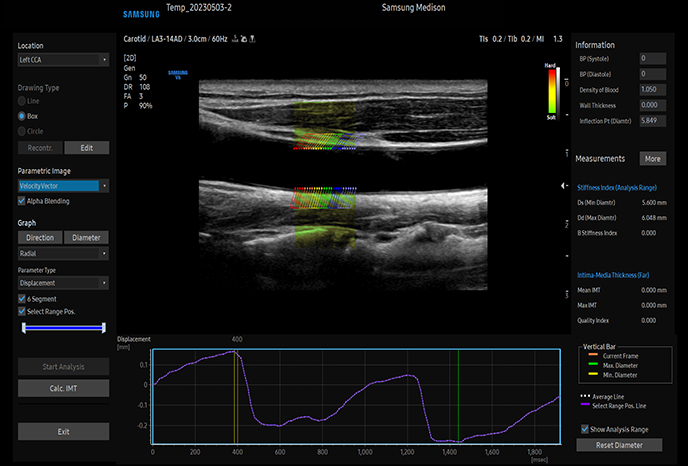

자동 IMT(경동맥 내막두께) 측정

동맥 분석